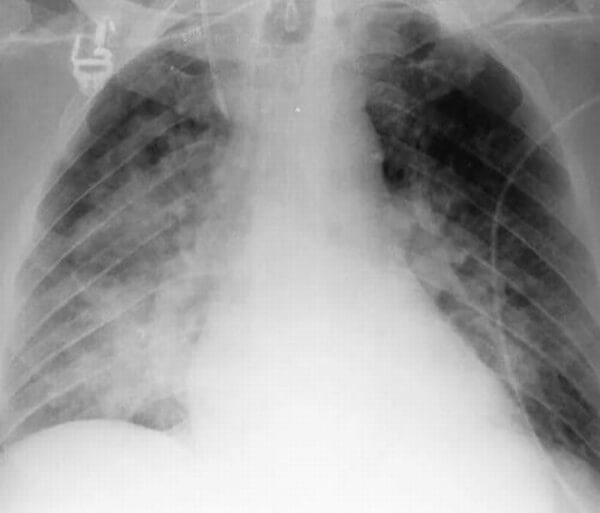

Абсцедирующая

При абсцедирующей пневмонии на снимке отчетливо видно тотальное затемнение области инфильтрации и уплотнение плевры; наблюдаются полости до 2 см, в которых скапливается гнойная жидкость.

Фотоснимок при абсцедирующей пневмонии